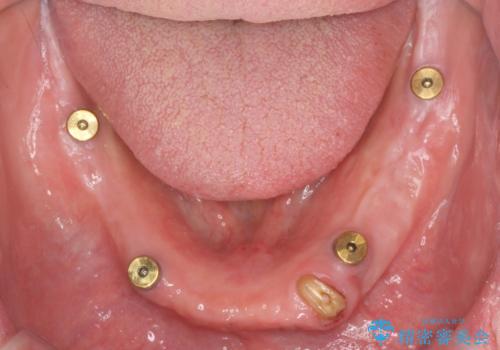

歯が折れている(1DAY インプラント)